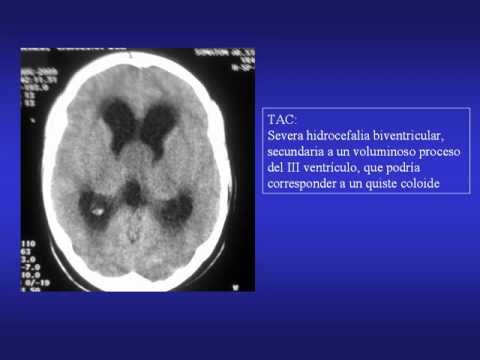

Se realiza un TAC craneal y se observa, una severa hidrocefalia biventricular, secundaria a un voluminoso proceso del III ventrículo, que podría corresponder a un quiste coloide.

En el TAC de control postoperatoria se observa reducción de ambos ventrículos laterales.